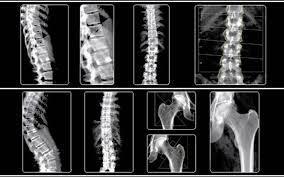

Η μέτρηση της οστικής πυκνότητας γίνεται στην οσφυϊκή μοίρα της σπονδυλικής στήλης πριν από την ηλικία των 60 ετών ή στο άνω άκρο του μηριαίου οστού στην ηλικία των 60 ετών και πάνω. Για τη μέτρηση αυτή η πιο χρήσιμη και αξιόπιστη μέθοδος είναι η μέτρηση της απορρόφησης διπλοενεργειακών φωτονίων, που είναι γνωστή ως DEXA από το Dual Energy X-ray absorptiometry.

- Αφού λοιπόν αποφασίσουμε σε ποιό μηχάνημα θα κάνουμε την πρώτη μέτρηση οστικής πυκνότητας ή την επανάληψή της, θα πρέπει ο γιατρός να αποφασίσει σε ποιο σημείο του σώματος θα πρέπει να γίνει η εξέταση. Για την πλήρη κάλυψη κάθε ενδεχόμενου η μέτρηση θα πρέπει να γίνεται στην οσφυϊκή μοίρα της σπονδυλικής στήλης και στο δεξί και αριστερό ισχίο. Στην περίπτωση που η σπονδυλική στήλη υποφέρει από βαριά σκολίωση και εκφυλιστική σπονδυλοαρθρίτιδα η μέτρηση θα οδηγήσει σε πλάνη. Επίσης, από τα δύο ισχία προτιμάμε να μετρήσουμε το μη επικρατές (για δεξιόχειρες το αριστερό ισχίο και για αριστερόχειρες το δεξί ισχίο, αν και εφόσον στην εκεί περιοχή δεν έχει γίνει κάποια χειρουργική επέμβαση στο οστό).